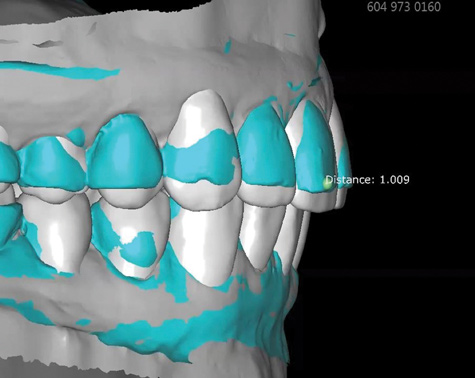

Fig 8. Scans are used to mock-up desired restorative results using modeling software. The teal-green areas represent the current tooth form, and the white areas show the desired or digital wax-up. A reduction of 1.009 mm was required prior to preparation, making endodontic treatment likely if orthodontic treatment is not considered.

Figure 8

Fig 9. Scans are used to mock-up desired restorative results using modeling software. The teal-green areas represent the current tooth form, and the white areas show the desired or digital wax-up. A reduction of 1.009 mm was required prior to preparation, making endodontic treatment likely if orthodontic treatment is not considered.

Figure 9